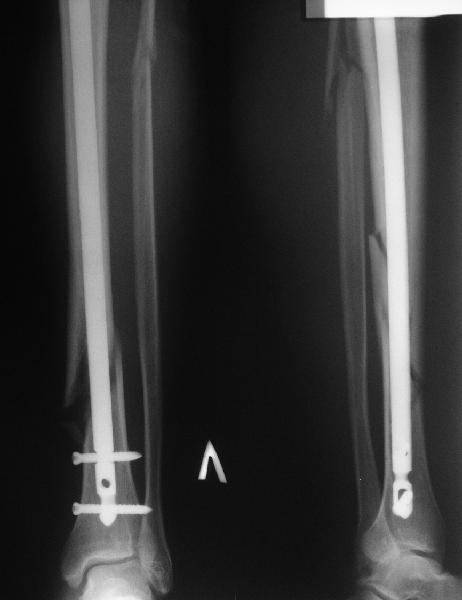

Все наши сомнения связаны с тем, что этих незначительных погрешностей (небольшой вальгус, неглубоко пробит гвоздь, мало запирающих винтов в

дистальном отломке) не одна, а несколько, и вместе они могут значительно осложнить дальнейшую жизнь пациенту. В нашей практике были подобные случаи, при которых после разрешения полной нагрузки либо начинала увеличиваться деформация, либо происходил перелом гвоздя по ближайшему отверстию. Кроме того, при диафизарных переломах, имея в арсенале надежный фиксатор, нет никакой необходимости вынуждать пациента ограничивать нагрузку на ногу в течении 2-3 месяцев.

Взвесив все <<за>> и <<против>>, мы приняли решение и выполнили реостеостинтез: выбили гвоздь до линии перелома, провели отклоняющую

спицу, забили обратно гвоздь и заблокировали внизу 3-мя винтами, вверху одним. Вся операция заняла меньше часа. Сегодня пациент ушел от нас домой с полной нагрузкой на ногу.

Здесь проблема не в идеальности репозиции, а в запасе усталостной прочности. Срастаться там может небыстро, диастазы довольно большие.

И когда еще и отломок короткий, и отверстие совсем рядом, это может привести к перелому стержня. За последние годы у нас было несколько пациентов, оперированных в других учреждениях с

подобным положением отломков, с такими переломами гвздей. И сейчас переделать куда как проще и легче, чем иметь дело со сломанным гвоздем.